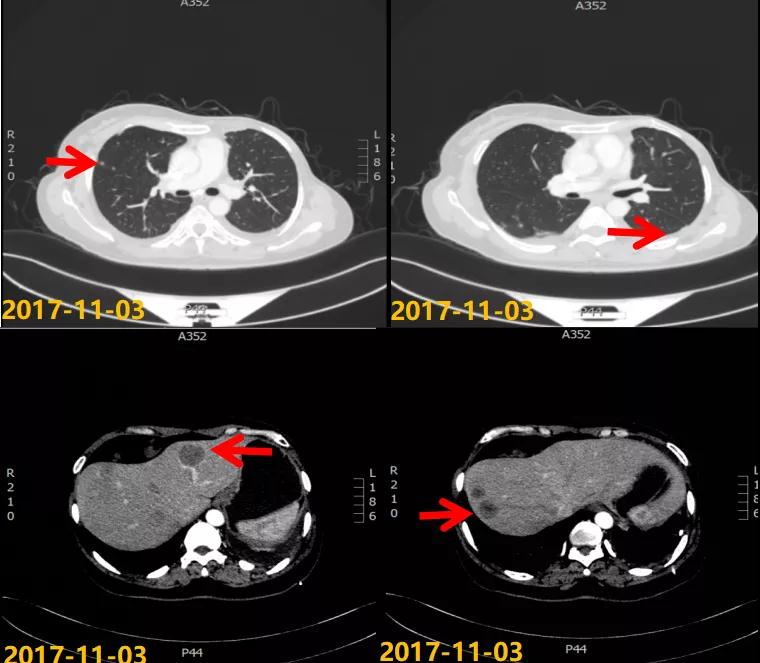

第一次病情进展: 2017-10-22患者因“气喘气憋、呼吸困难20天”就诊我院,胸水超声提示左侧大量胸腔积液,行胸水穿刺引流,查见癌细胞。2017-11-03 CT:两肺多发结节,考虑转移瘤;左侧胸膜斑块状增厚,提示胸膜转移;肝脏多发转移瘤。进一步行肝脏肿块穿刺活检,病理:ER(2+,90%),PR(3+,80%),HER2(2+),Ki-67(+,40%),FISH检测:未观测到基因扩增。

2017-11至2018-03:TX方案6周期(多西他赛120mg d1+卡培他滨1500mg po bid d1-14),化疗期间继续戈舍瑞林3.6mg ih q4w。疗效评估:前四周期略缩小但未达PR,后两周期SD,呼吸道症状明显改善。2018-04行戈舍瑞林3.6mg ih q4w联合氟维司群 500mg im q4w内分泌维持治疗,同时经MDT多学科讨论后行肝脏射频消融术。一线治疗获得36个月PFS。